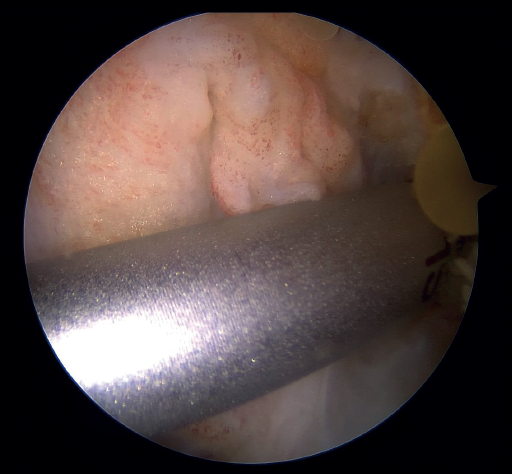

The next step consists of introducing the necessary instruments through the anteromedial portal to make several perforations approximately 1 mm deep in the femoral insertional footprint, with the aforementioned aim of obtaining a bleeding bed to facilitate healing of the ACL. Such drilling can be done manually (with micro- or nanofracture punches) or motorized (PowerPick®, Arthrex), and this step is usually made easier by flexing the knee at about 100°.

Once the bone marrow is stimulated, a short silicone cannula (PassPort®) is placed in the anteromedial portal with the help of vascular forceps. This cannula will help us to organize the suture threads and will make it difficult for Hoffa's fat pad and other soft tissues to get in the way. With the same aim of facilitating suture management (and drilling of the femoral tunnel), an accessory medial portal is now added, in a position medial to the anteromedial portal.

The femoral tunnel is made from this accessory medial portal using a 4.5 mm diameter spear point drill, from the most anterior portion of the insertional footprint of the ACL through the lateral cortex of the femur. Once the tunnel has been completed, the same drill is used to leave a retriever thread through the femoral tunnel, as it is equipped with an eyelet. It is important to secure the two ends of this thread together outside of the knee in order to avoid losing either of them during surgery.